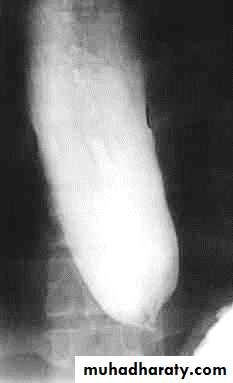

PULSION DIVERTICULUM

Due to:

raised intra-luminal tension

Chocking after meal .

In cervical portion at level of C5

Posteriorly (Killience dehiscent)

Lateral view show increased pre-vertebral space with air fluid level.

Confirmed by Ba. Swallow.

TRACTION DIVERTICULUM

Out pouching of lumen laterally due to fibrosis & adhesions ( post-Tb.)

In the middle third at level of hilum

Up ward direction of diverticulum

Irregular base

On the far left a traction diverticulum (arrow) due to hilar granulomatous disease. Calcified adenopathy (asterisk).

In the middle a pulsion diverticulum (arrow) due to high intra luminal pressure.

On the right multiple pulsion diverticula (arrows)

CONGENITAL DIVERTICULUM

Asymtomatic unless complicated.

At lower part of esophagus above the diaphragm (Epi-phrenic)

Lateral or posterior in position.